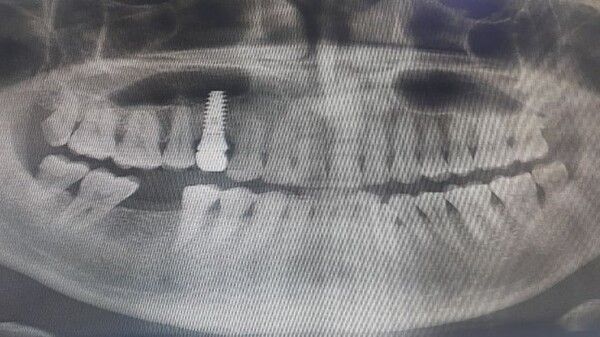

사진 = 뉴시스